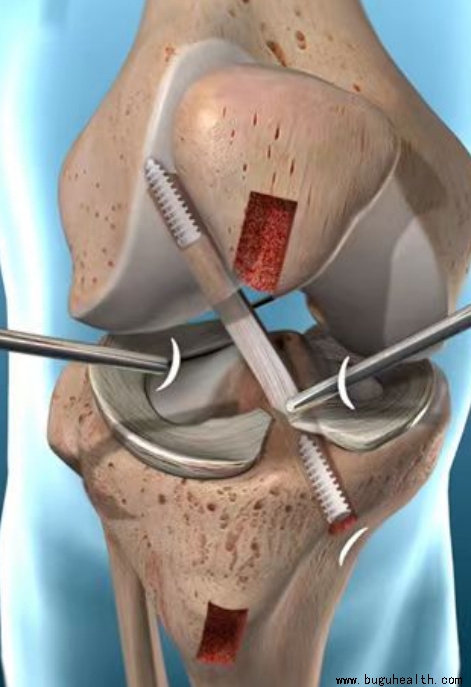

- 布骨医学科普:前交叉韧带重建术后需要重视的问题! BuGuRMC布骨康复医疗中心 ,2024-05-28

- 前交叉重建术是一种常见的关节手术,通常用于修复膝关节前交叉韧带(ACL)的撕裂或损伤。术后康复是确保手术成功和患者恢复功能的关键。那么术后除了康复训练之外还需要的是术后需要重视的问题,今天一起来看一下。.....